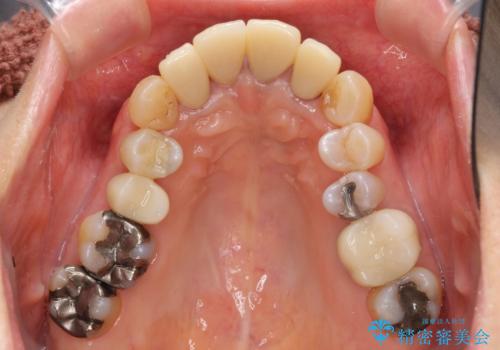

- 上顎前歯の黒ずみの改善、下顎前歯の十度なガタつき、矯正治療とセラミック治療を含む全体的な治療を希望され来院されました。

銀歯を高強度の仮歯に替えたのち、下顎前歯のみの部分矯正→全体的なマウスピース矯正治療(インビザライン)→最終的なセラミック治療と治療を進めます。